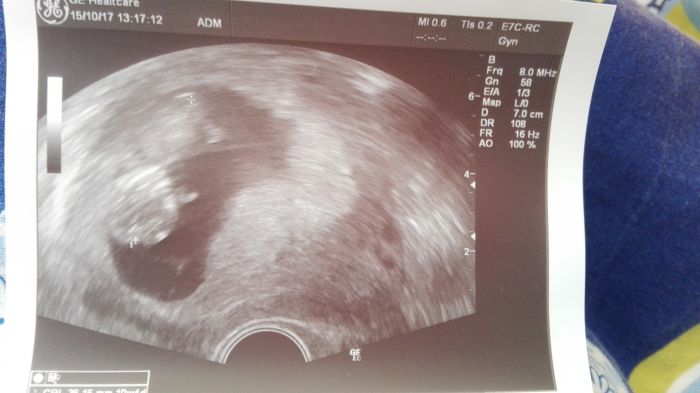

Ahojky maminy, tak jsem byla na krvi a na ultrazvuk do Gennetu jdu 31.10. Kontrola dnes ok, 11tt. No už bych ráda též věděla, co to bude. Chci nakupovat.... Ale to si ještě počkám. Všem co jdou na kontrolu, tak držím pesticky